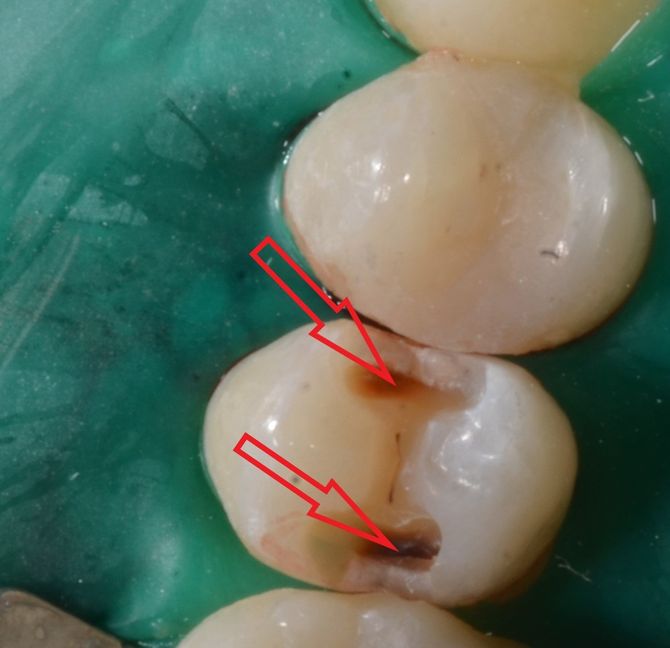

Viene presentato un caso in cui si evidenzia la presenza di carie mesiale e distale su un 25 (secondo premolare superiore di destra) attraverso l'analisi radiografica. Si deve sottolineare la difficoltà di metterne in risalto e di determinarne l'estensione solo mediante la radiografia. Nella fotografia successiva, l'entità e l'estensione della carie appaiono notevolmente superiori a quanto potesse essere dedotto dalla sola radiografia. Si mostra poi la cavità ripulita dalla carie, evidenziando la perdita di tessuto dentale causata da essa. Infine, si presenta l'otturazione appena completata, con i segni della cartina da articolazione ancora visibili, utilizzata per verificare l'altezza della cura, che richiederà successivamente un ulteriore rifinitura e lucidatura.

Un particolare utilizzo di due fasci laser e di un sensore che trasforma la transilluminazione in immagine visibile sul monitor del computer trova un utilizzo anche nella diagnosi della carie qualora l’immagine radiografica risulti dubbia o non dirimente di lesione cariosa. Ecco un esempio in cui radiologicamente si vede un’immagine non chiaramente rapportabile ad una carie come indicato dalle frecce nella radiografia a fianco. Con l’ausilio del laser si riesce ad evidenziarne completamente i limiti e la grandezza come visibile dalle due immagini e dalle frecce che indicano la carie. Tuttavia, per correttezza, va spiegato che l’efficacia di questa indagine può essere effettuata solo in determinate circostanze cliniche e che le radiografie risultano sempre necessarie.